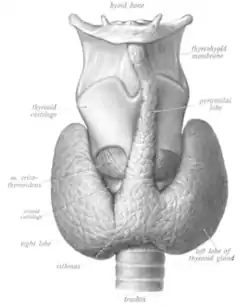

The thyroid gland is a butterfly-shaped organ composed of two lobes, left and right, connected by a narrow tissue band, called an "isthmus".[4] It weighs 25 grams in adults, with each lobe being about 5 cm long, 3 cm wide, and 2 cm thick and the isthmus about 1.25 cm in height and width.[4] The gland is usually larger in women than in men, and increases in size during pregnancy.[4][5]

The thyroid is near the front of the neck, lying against and around the front of the larynx and trachea.[4] The thyroid cartilage and cricoid cartilage lie just above the gland, below the Adam's apple. The isthmus extends from the second to third rings of the trachea, with the uppermost part of the lobes extending to the thyroid cartilage and the lowermost around the fourth to sixth tracheal rings.[6] The infrahyoid muscles lie in front of the gland and the sternocleidomastoid muscle to the side.[7] Behind the outer wings of the thyroid lie the two carotid arteries. The trachea, larynx, lower pharynx and esophagus all lie behind the thyroid.[5] In this region, the recurrent laryngeal nerve[8] and the inferior thyroid artery pass next to or in the ligament.[9] Typically, four parathyroid glands, two on each side, lie on each side between the two layers of the thyroid capsule, at the back of the thyroid lobes.[4]

Sometimes there is a third lobe present called the pyramidal lobe.[5] When present, this lobe often stretches up to the hyoid bone from the thyroid isthmus and may be one to several divided lobes.[4] The presence of this lobe ranges in reported studies from 18.3%[11] to 44.6%.[12] It was shown to more often arise from the left side and occasionally separated.[11] The pyramidal lobe is also known as Lalouette's pyramid.[13] The pyramidal lobe is a remnant of the thyroglossal duct, which usually wastes away during the thyroid gland's descent.[5] Small accessory thyroid glands may in fact occur anywhere along the thyroglossal duct, from the foramen cecum of the tongue to the position of the thyroid in the adult.[4] A small horn at the back of the thyroid lobes, usually close to the recurrent laryngeal nerve and the inferior thyroid artery, is called Zuckerkandl's tubercle.[9]

Other variants include a levator muscle of thyroid gland, connecting the isthmus to the body of the hyoid bone,[5] and the presence of the small thyroid ima artery.[5]